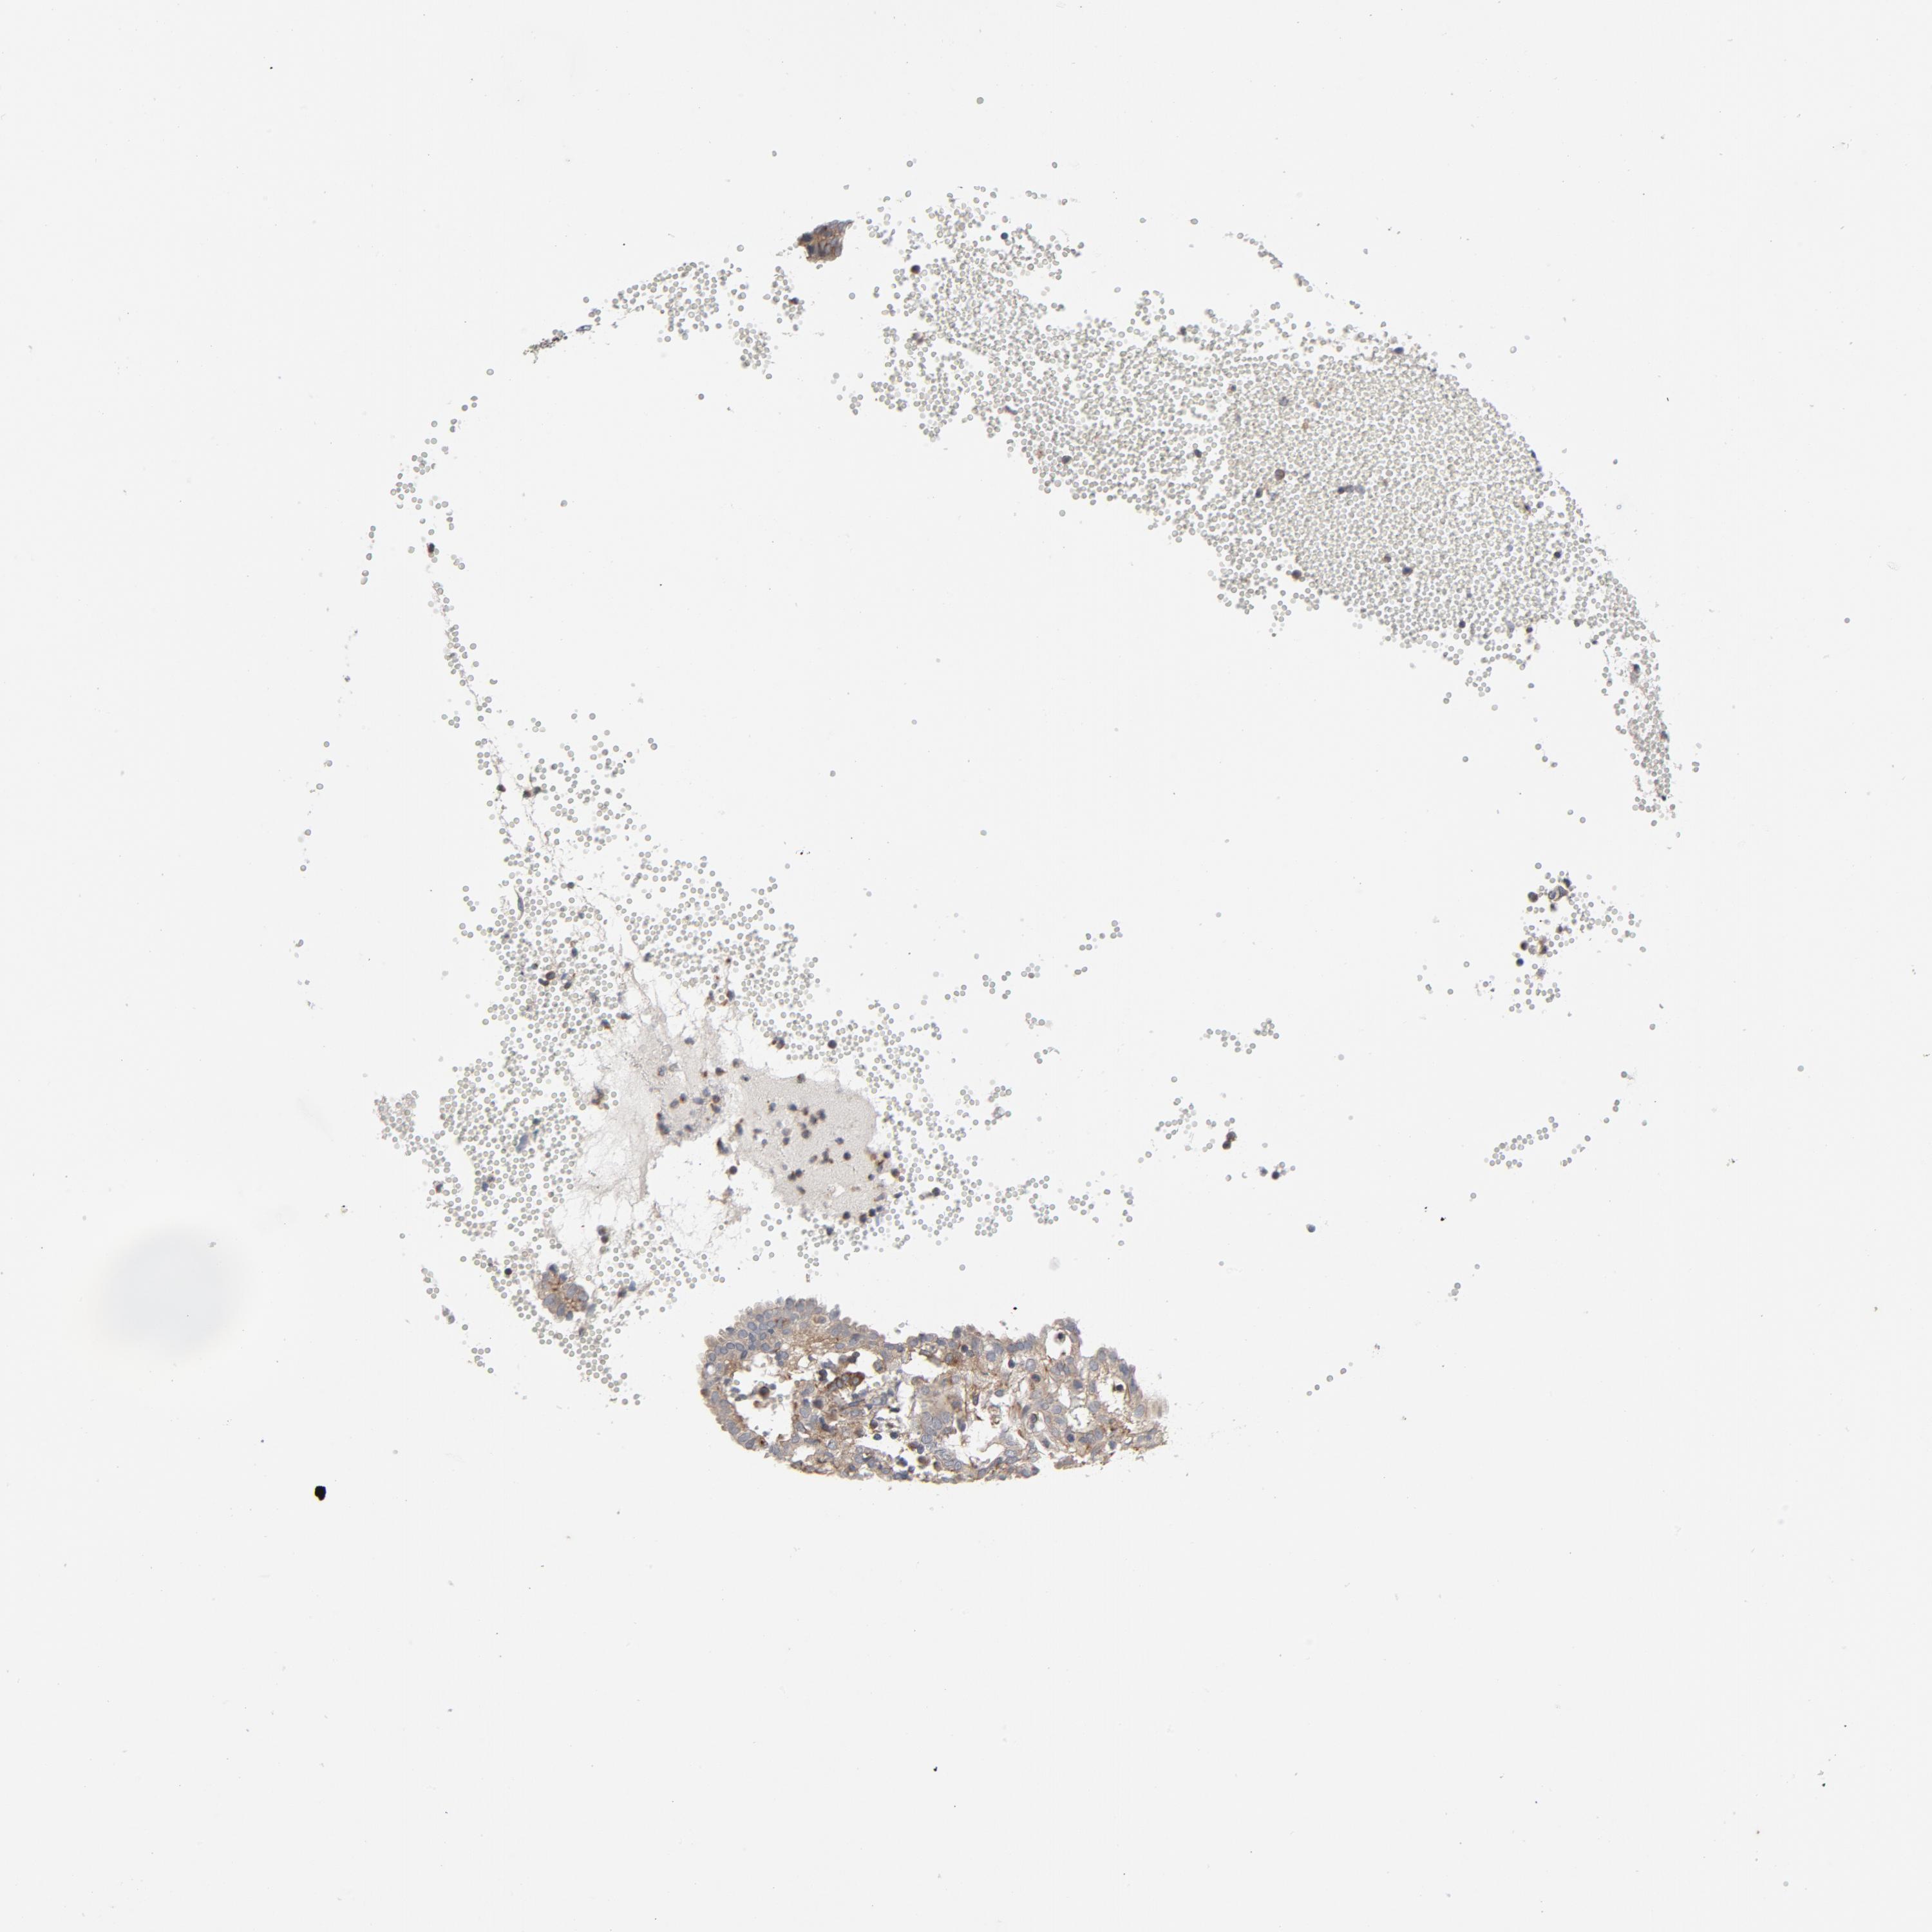

ENDOMETRIAL CANCER - Protein expressioni

A mouse-over function shows sample information and annotation data. Click on an image to view it in a full screen mode. Samples can be filtered based on level of antibody staining by selecting one or several of the following categories: high, medium, low and not detected. The assay and annotation is described here.

Note that samples used for immunohistochemistry by the Human Protein Atlas do not correspond to samples in the TCGA dataset.

Antibody stainingi

Antibody staining in the annotated cell types in the current human tissue is reported as not detected, low, medium, or high, based on conventional immunohistochemistry profiling in selected tissues. This score is based on the combination of the staining intensity and fraction of stained cells.

Each image is clickable and will lead to virtual microscopy that enables deeper exploration of all samples and also displays staining intensity scores, fraction scores and subcellular localization as well as patient and tissue information for each sample.

Antibody HPA003747

Antibody HPA019769

Staining

High

Medium

Low

Not detected

Intensity

Strong

Moderate

Weak

Negative

Quantity

>75%

75%-25%

<25%

None

Location

Nuclear

Cytoplasmic/membranous

Cytoplasmic/membranous,nuclear

Adenocarcinoma, NOS

Adenoma, NOS